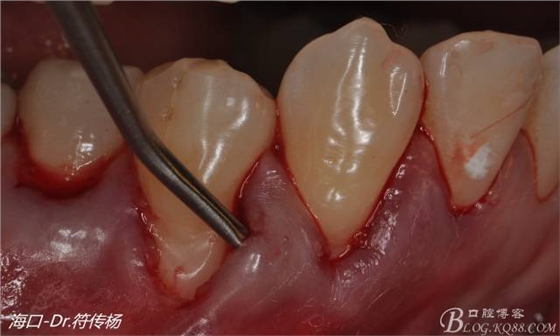

接著從腭部上皮下取出結(jié)締組織

確定取出結(jié)締組織長(zhǎng)度是否適當(dāng)

腭部使用水平懸吊縫合更利于壓迫止血

受植區(qū)建議使用雙交叉垂直懸吊縫合術(shù)來(lái)固定結(jié)締組織并能讓齦瓣更貼合根面利于術(shù)后一期愈合